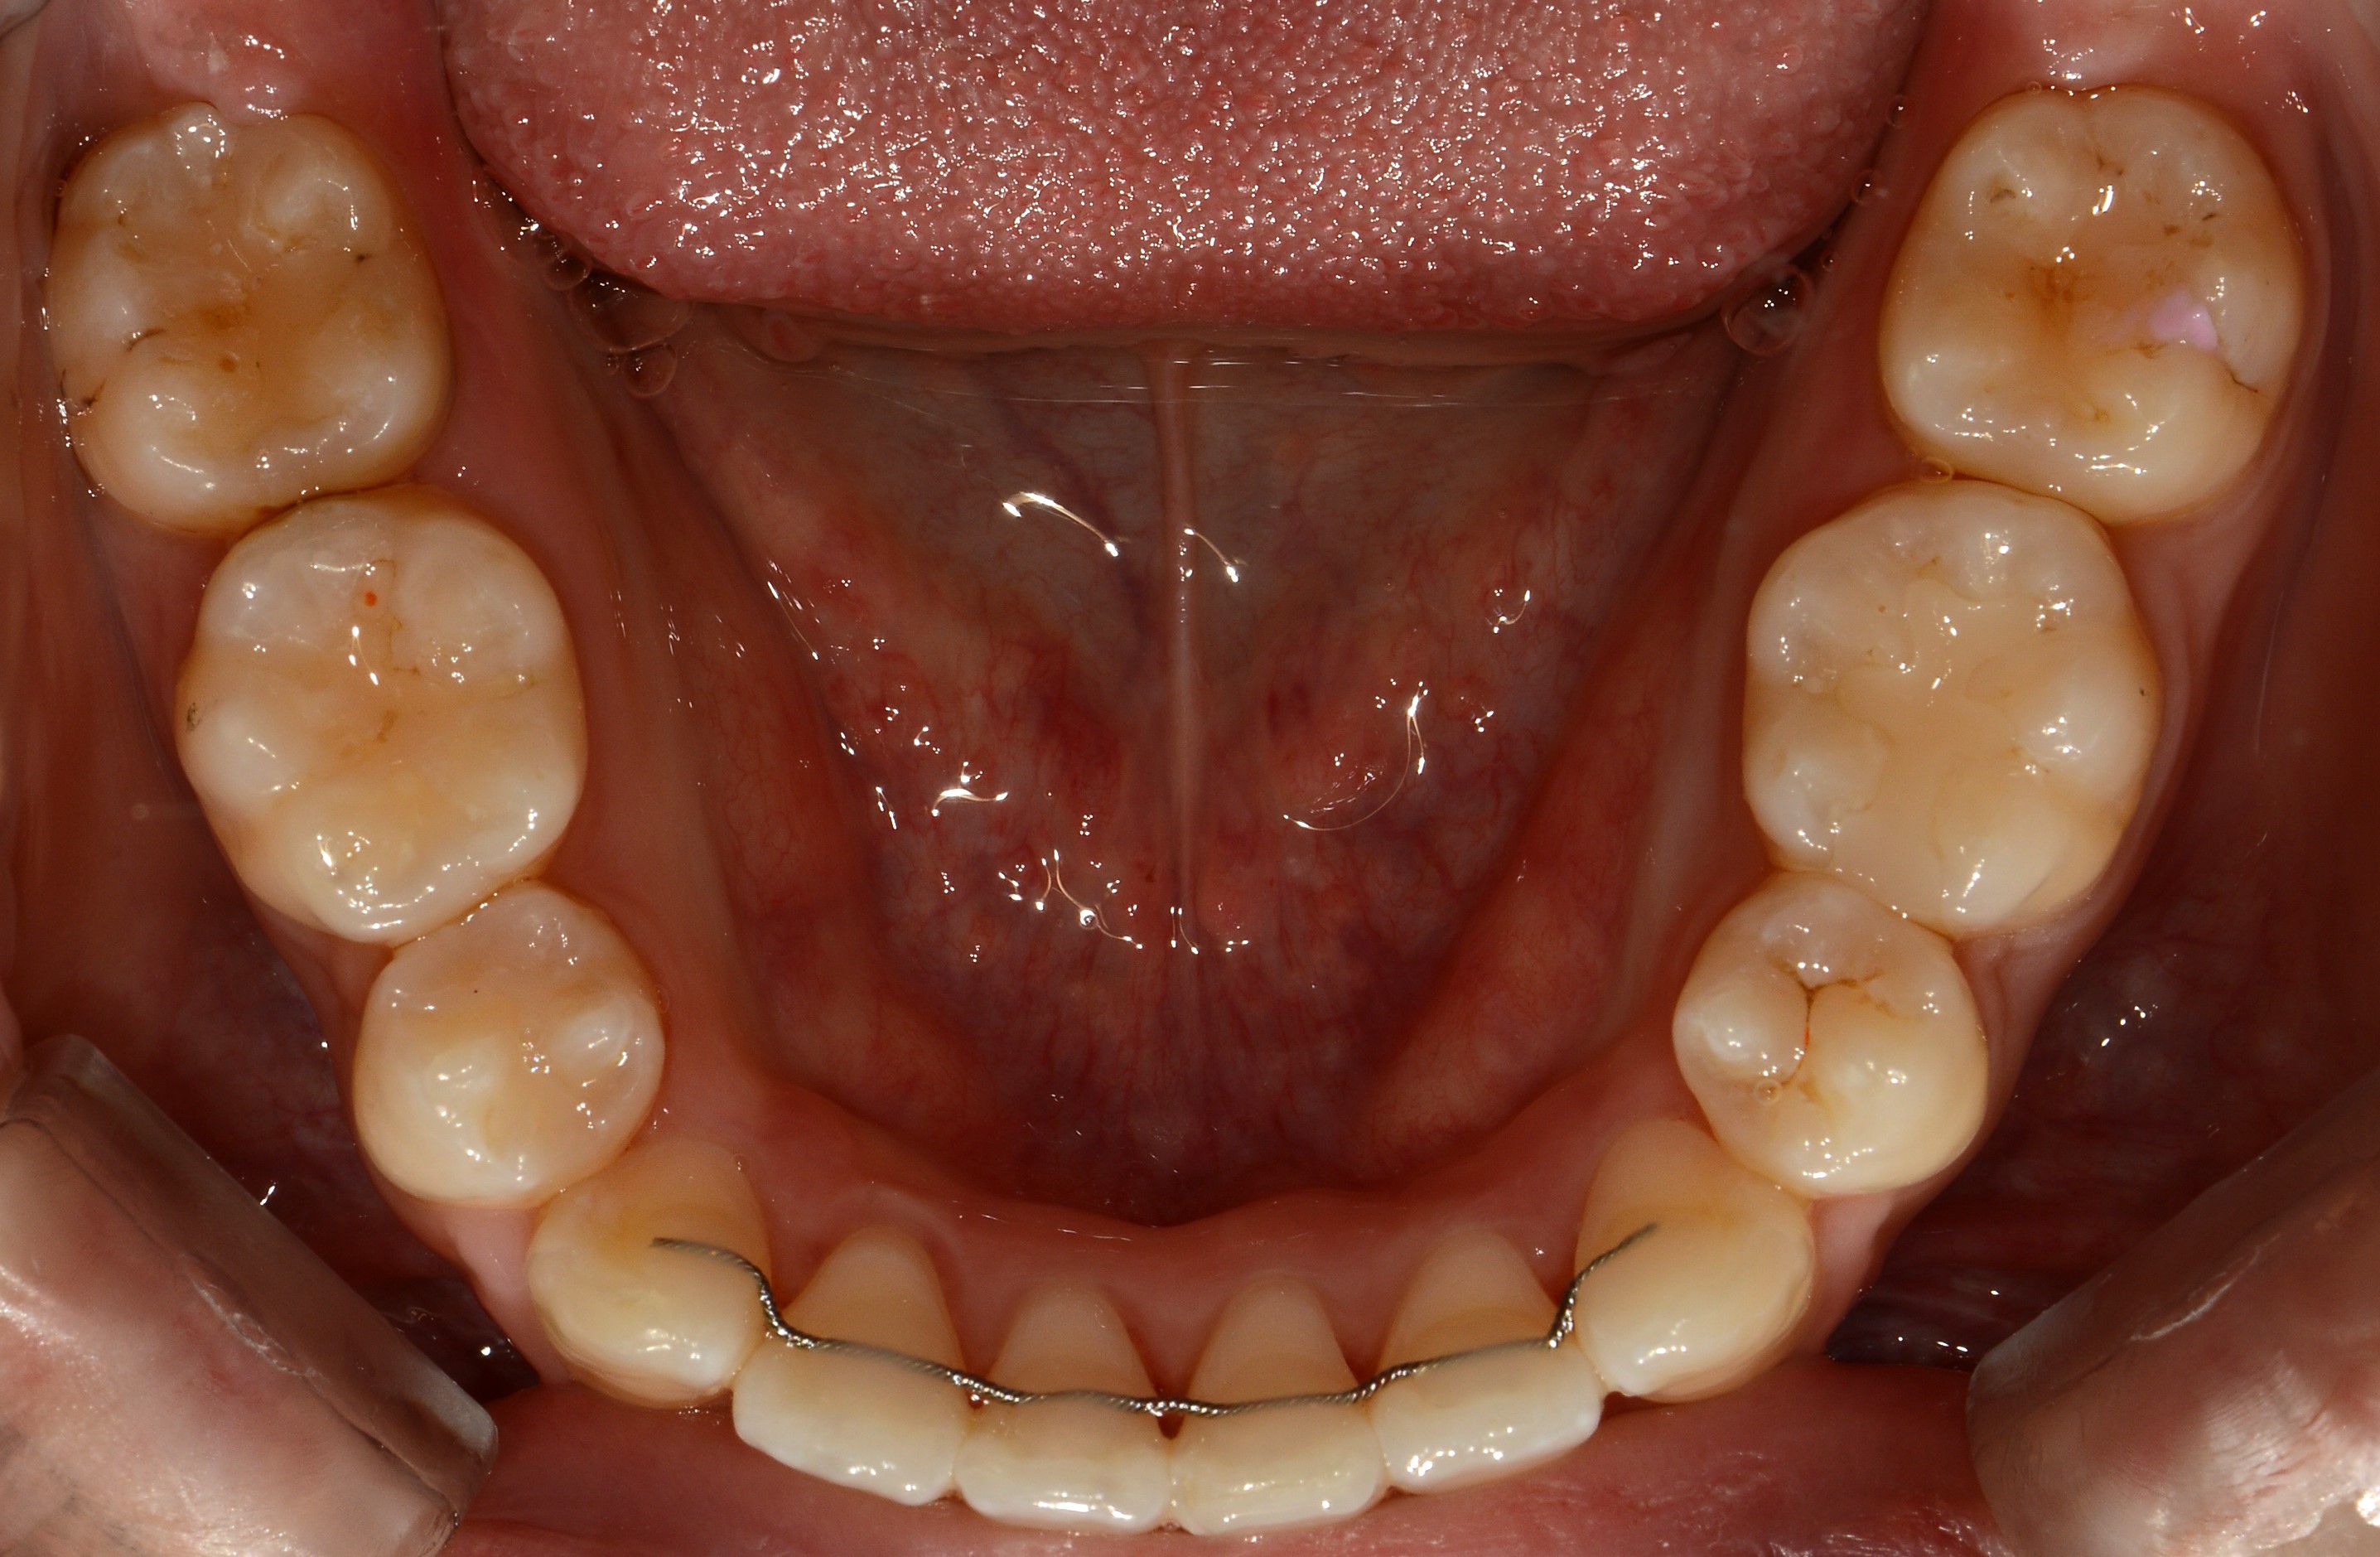

치료 전 사진입니다.